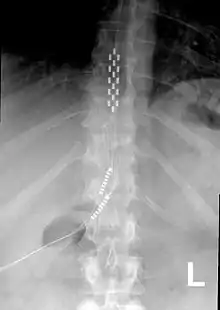

عرض أمامي بواسطة ألاشعة السينية للحبل الشوكي المحفز (SCS) مزروع في العمود الفقري الصدري

محفز الحبل الشوكي أو مشجع الحبل الشوكي (بالإنجليزية: spinal cord stimulator) هو جهاز يستخدم لتسليط إشارات كهربائية نابضة إلى الحبل الشوكي للسيطرة على الألم المزمن. بالإضافة إلى تطبيقات اخرى في مجال الاضطرابات الحركية. الحبل الشوكي القطني هو الهدف المفضل للتحكم في التشنج الشوكي [1][2] أو تكبير وزيادة القدرة على الحركة أو الوقوف لدى المرضى.[3][4][5][6]